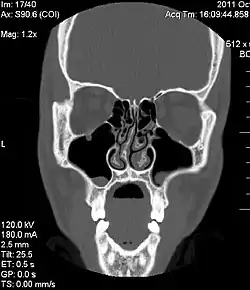

![]() A CT scan of the head showing the inner workings of the nose with a deviated septum صورة طبقية توضح انحراف الوتيرة الأنفية الخلقي | |